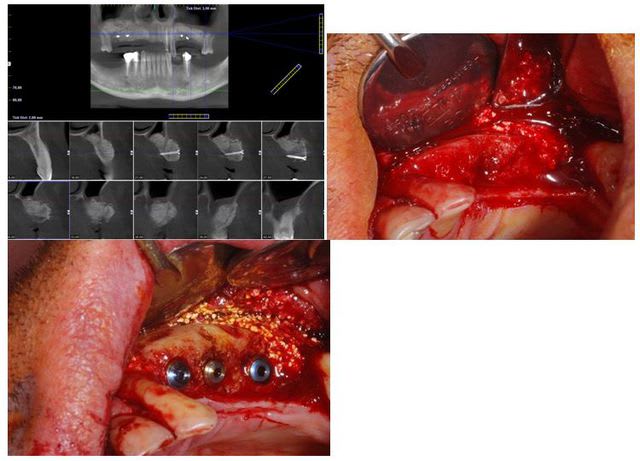

ce matin implantation à 5 mois post sinus lift + greffe onlay Biobank. Très bonne stabilité primaire.

Planche 1 fx9sim - Eugenol

Planche 2 k3neab - Eugenol

la résorption était majoritairement vestibulaire

les forages ont été effectués volontairement dans le couloir prothétique ce qui les a situé pratiquement à la jonction entre la crête résiduelle et le greffon et cela laisse ici justement une bonne épaisseur de matériau greffé en vestibulaire en prévision d'une éventuelle future résorption.

après voilà, nous verrons si la résorption sera GARANTIE, garantie ou absente.